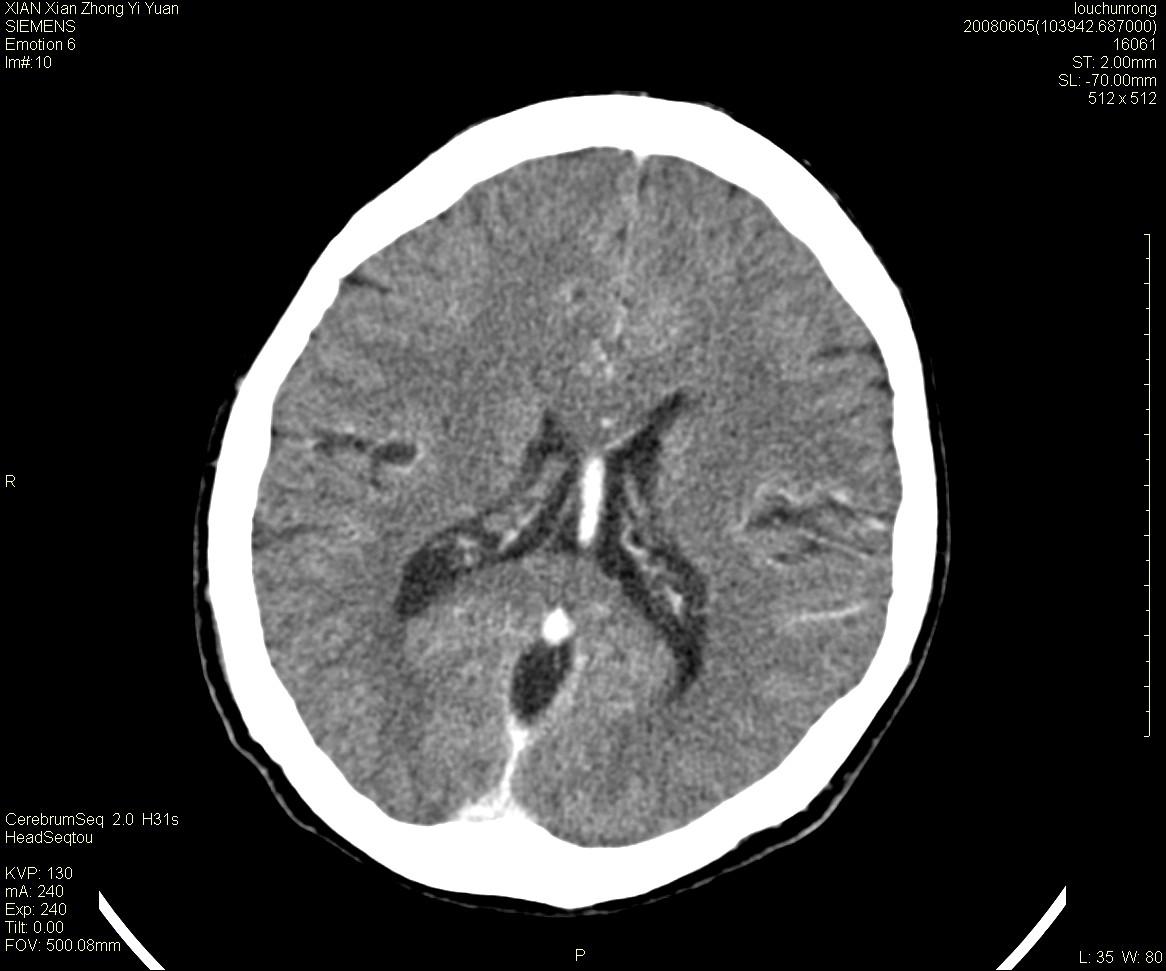

标题: CT13860:F52Y,,头外伤致头晕半天,以前无不适。 [打印本页]

标题: CT13860:F52Y,,头外伤致头晕半天,以前无不适。

层厚2mm。

左侧侧室内血管异常增粗,考虑血管变异或血管瘤可能,余未见异常

静脉窦血栓? mri检查

两侧脑室体部距离增宽,胼胝体发育不良?

侧脑室前角变形、变窄,考虑侧脑室粘合;余未见明显异常。